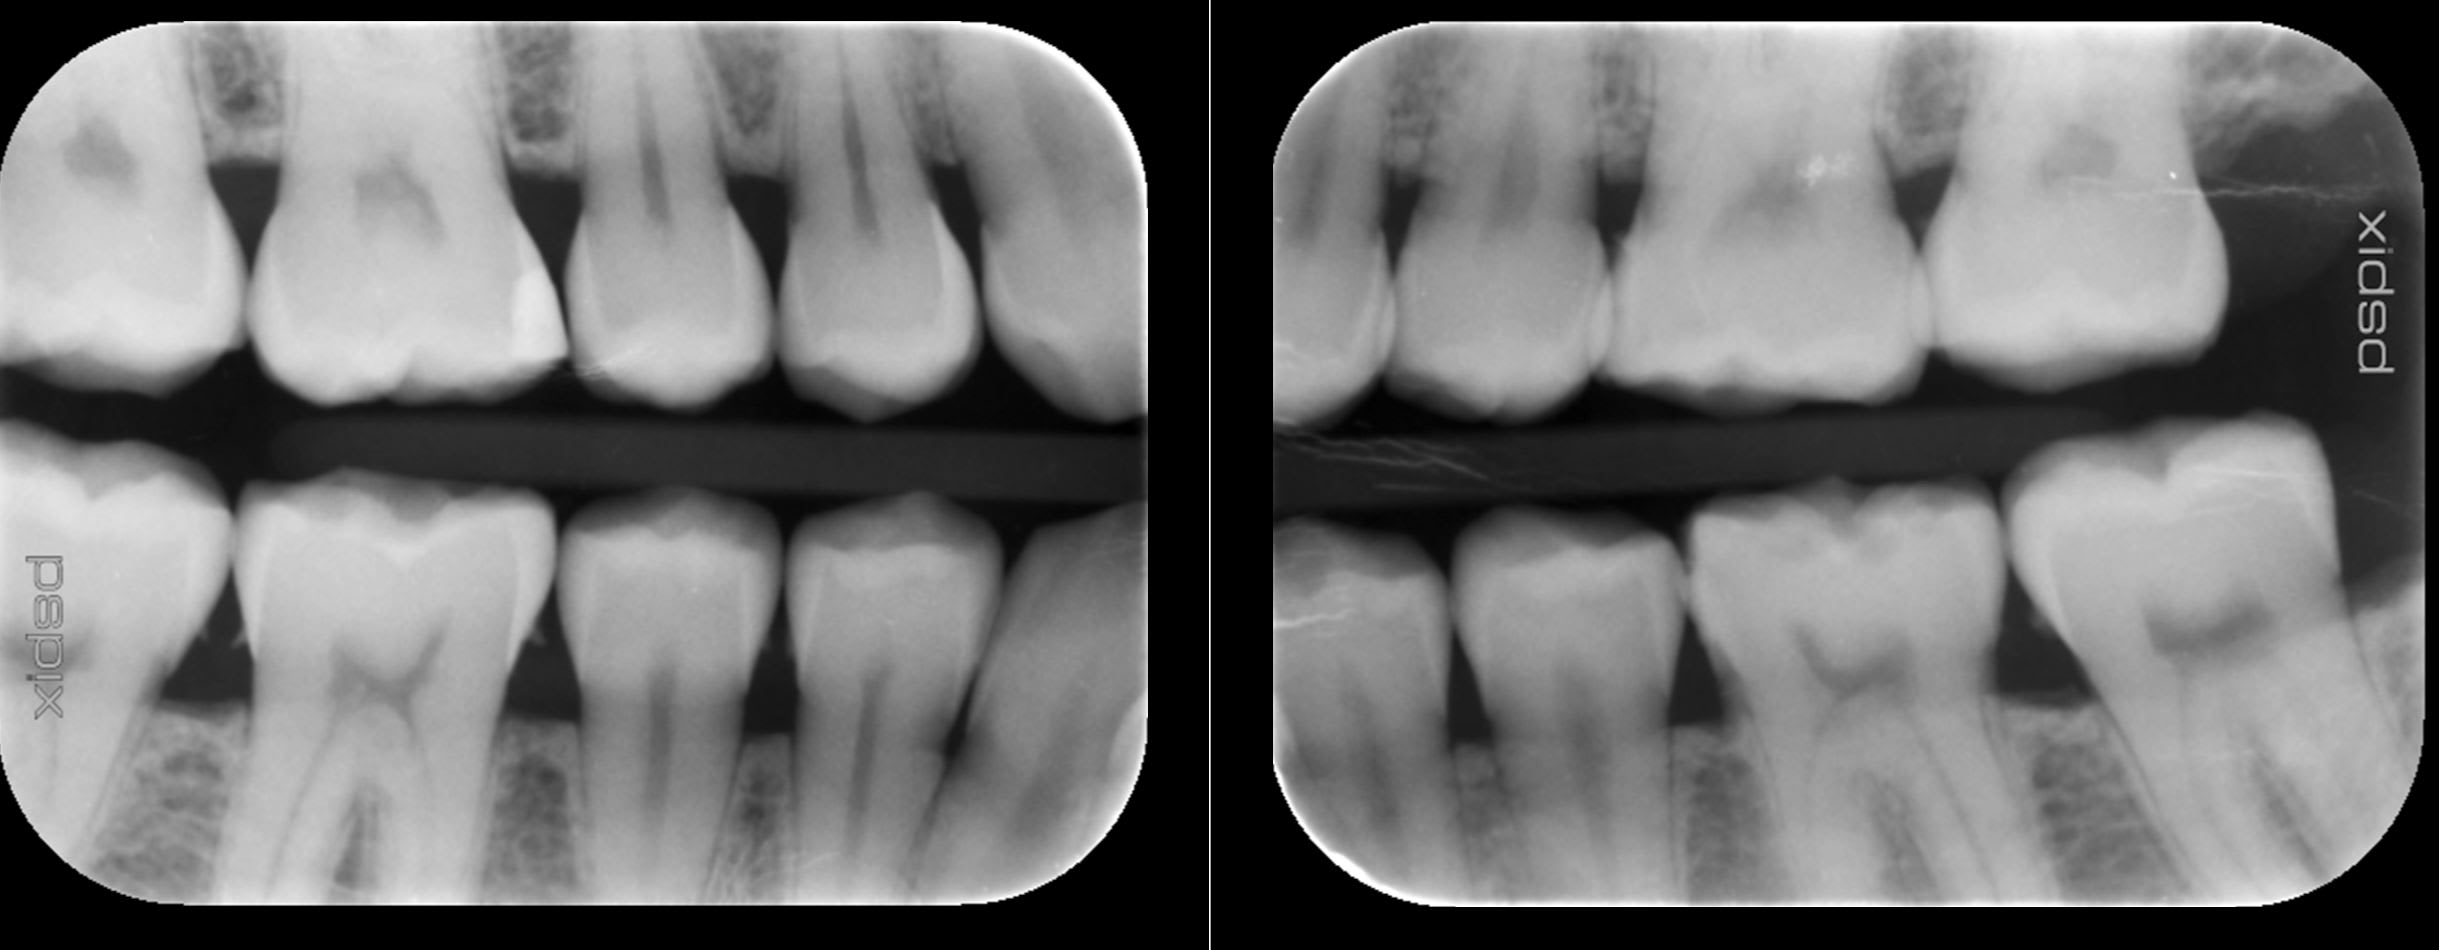

Que proposer à mon patient de 31 ans, pratique sportive régulière (juste de l'eau, rarement du sucre), non fumeur, avec une usure assez marquée des molaires (a priori je dirai des usures d'origine chimique associée à du bruxisme) dont je vous joins ici les photos.

Les molaires étaient sensibles il y a quelques mois à l'alimentation, mais depuis la fluoration et l'utilisation de dentifrice adapté (Mirasensitive HAP+), les sensibilités apparaissent uniquement lorsque j'utilise une sonde exploratrice sur la face occlusale.

Les usures évoluent sensiblement d'année en année (suivi photo).

Il a consulté un gastro entérologue, qui n'a trouvé aucune anomalie provoquée par une RGO.

Je pense continuer avec une gouttière occlusale, car il me rapporte avoir des contractures musculaires au réveil.

J'ai modifié les photos, j'avais posté 2x la machoire supérieure, mais pas l'inférieure qui est plus usée, nott sur 36. J'en rajoute un peu en voila dautres.

Pour moi j'étais certain du diagno de RGO, vu les faces occlusales, et vu les faces incisales des 42 à 32.